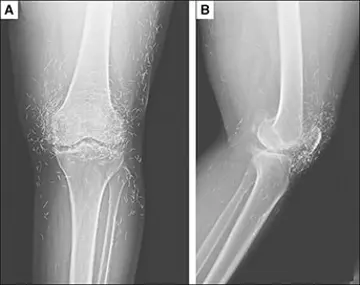

یک خانم 65 ساله به‌علت درد هر‌دو زانو مراجعه کرد...

بازبینی استئوآرتریت(۲) (بخش پایانی)